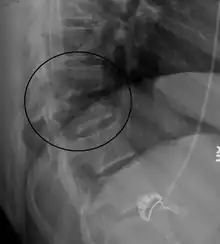

| A Chance fracture of T10 and fracture of T9 due to a seatbelt during an MVC. | |

A Chance fracture is a type of vertebral fracture that results from excessive flexion of the spine.[8][9] Symptoms may include abdominal bruising (seat belt sign), or less commonly paralysis of the legs.[4][10] In around half of cases there is an associated abdominal injury such as a splenic rupture, small bowel injury, pancreatic injury, or mesenteric tear.[3][5] Injury to the bowel may not be apparent on the first day.[11]

The cause is classically a head-on motor vehicle collision in which the affected person is wearing only a lap belt.[2] Being hit in the abdomen with an object like a tree or a fall may also result in this fracture pattern.[12][10] It often involves disruption of all three columns of the vertebral body (anterior, middle, and posterior).[7][6] The most common area affected is the lower thoracic and upper lumbar spine.[6] A CT scan is recommended as part of the diagnostic work-up to detect any potential abdominal injuries.[5] The fracture is often unstable.[1]